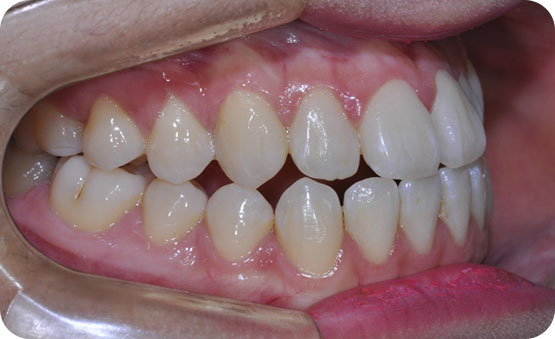

덧니교정( 청소년 교정:비 발치 교정 /악궁 확장장치+미니스크류+약간의 치간삭제 교정)

Before

After

※ 치간삭제는 다듬는 양이 많지 않아 생리적으로 허용되는 범주까지만 다듬는다면

심미적이며 부정교합의 재발도 줄일수 있는 방법 입니다